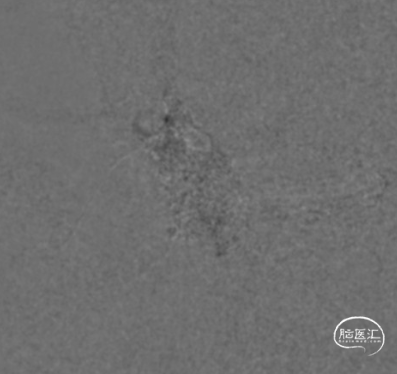

治疗经过

二期治疗